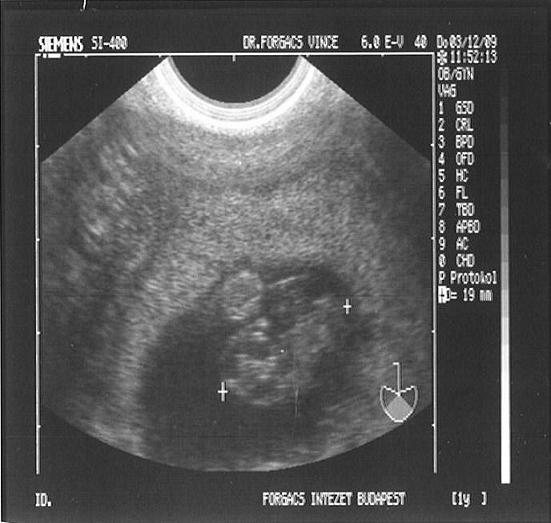

Én voltam dokinál szerdán, nem láttam Picurt, de hallottam a szívverését, és ez megnyugtatott kicsit. Várom már a 25-ét!!!!